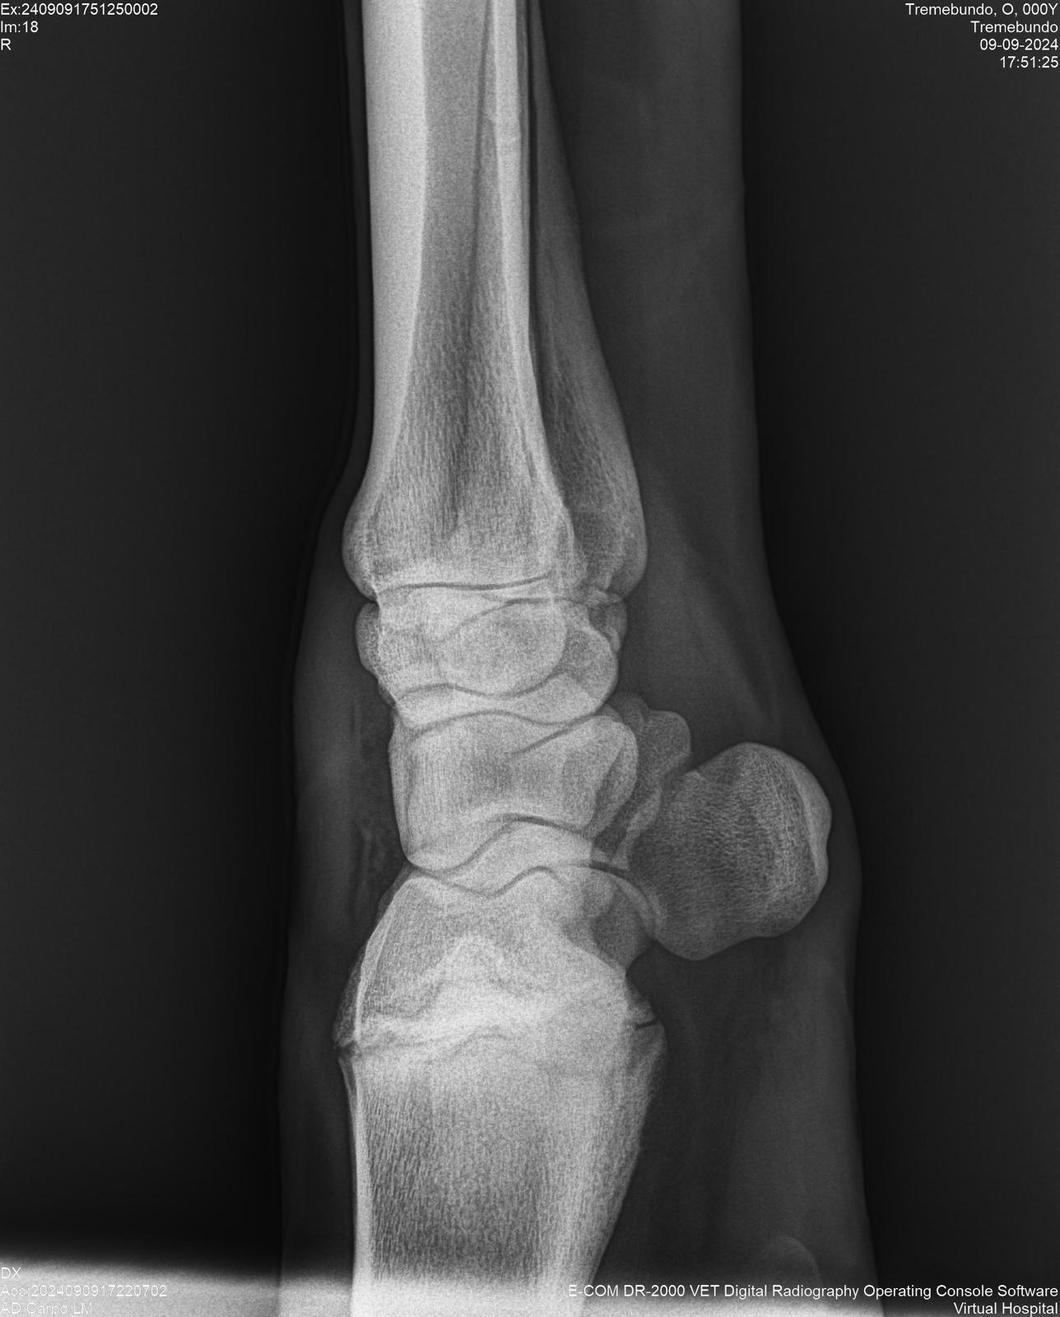

LOTE 37, TREMEBUNDO

Ficha del Lote

Identificador: #291140-

Generacion 2022